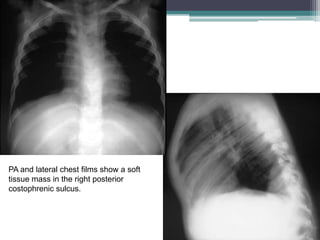

PA and lateral chest films show a soft

tissue mass in the right posterior

costophrenic sulcus.

Final Diagnosis:

Intrathoracic Kidney